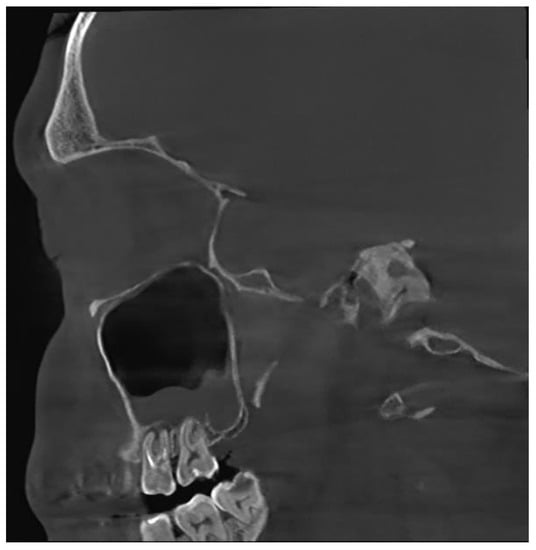

Unfortunately, nowadays, the most common cause of odontogenic sinusitis is iatrogenic harm (approximately 56%), with most cases occurring in patients who underwent dental interventions. Iatrogenic harm occurs upon incorrectly performed sinus lift procedures or implant placement, foreign bodies, dental extractions with or without pushing a fragment of the root into the sinus cavity, orthognathic surgery, labio-palatine cleft surgery, Le Fort osteotomies, inadequate oro-antral fistula closure procedures, periimplantitis or endodontic treatment failure (Figure 1).

Figure 1. CBCT image of odontogenic sinusitis caused by iatrogenic harm via failed endodontic treatment: upper first and second molar periodontitis, chronic apical periodontitis (sagittal view).